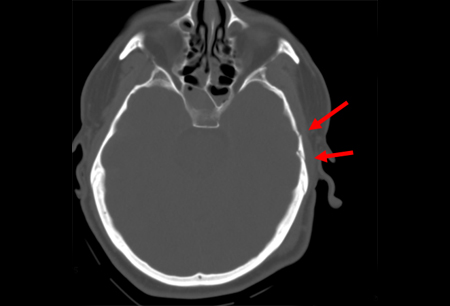

Occipital fracture extending to foramen magnum: risk of brainstem compression by hematoma